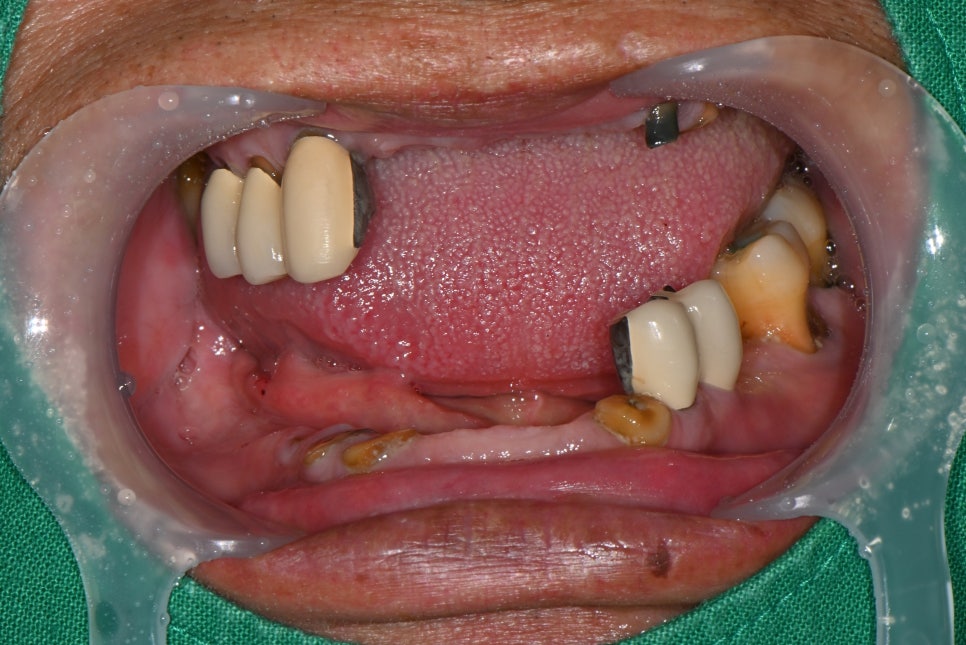

하악 보험 임플란트 식립 후 의 모습

한달 후 상악 전체 발치 진행한 모습

치료 과정

- 상악 치료: 발치 후 완전틀니 제작

불안정한 치아들을 발치한 후 잇몸을 안정화시키고

본을 떠 상악 완전틀니를 새로 제작했습니다.

- 하악 치료: 보험 임플란트 + 부분틀니

하악에는 보험 적용되는 2개의 임플란트를 식립했습니다.

임플란트가 잇몸에 잘 유착된 것을 확인한 후,

임플란트 고리를 이용한 보험 부분틀니를 제작했습니다.

기존보다 훨씬 안정적으로 고정되고, 이물감도 크게 줄었습니다.